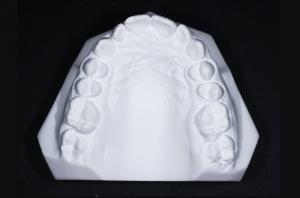

• Des empreintes dentaires pour obtenir des moulages d’étude

À partir des éléments de ce bilan orthodontique, le praticien va pouvoir analyser les données cliniques, les photos, les radiographies pour une analyse céphalométrique et les moulages pour établir un diagnostic précis et proposer un traitement adapté.